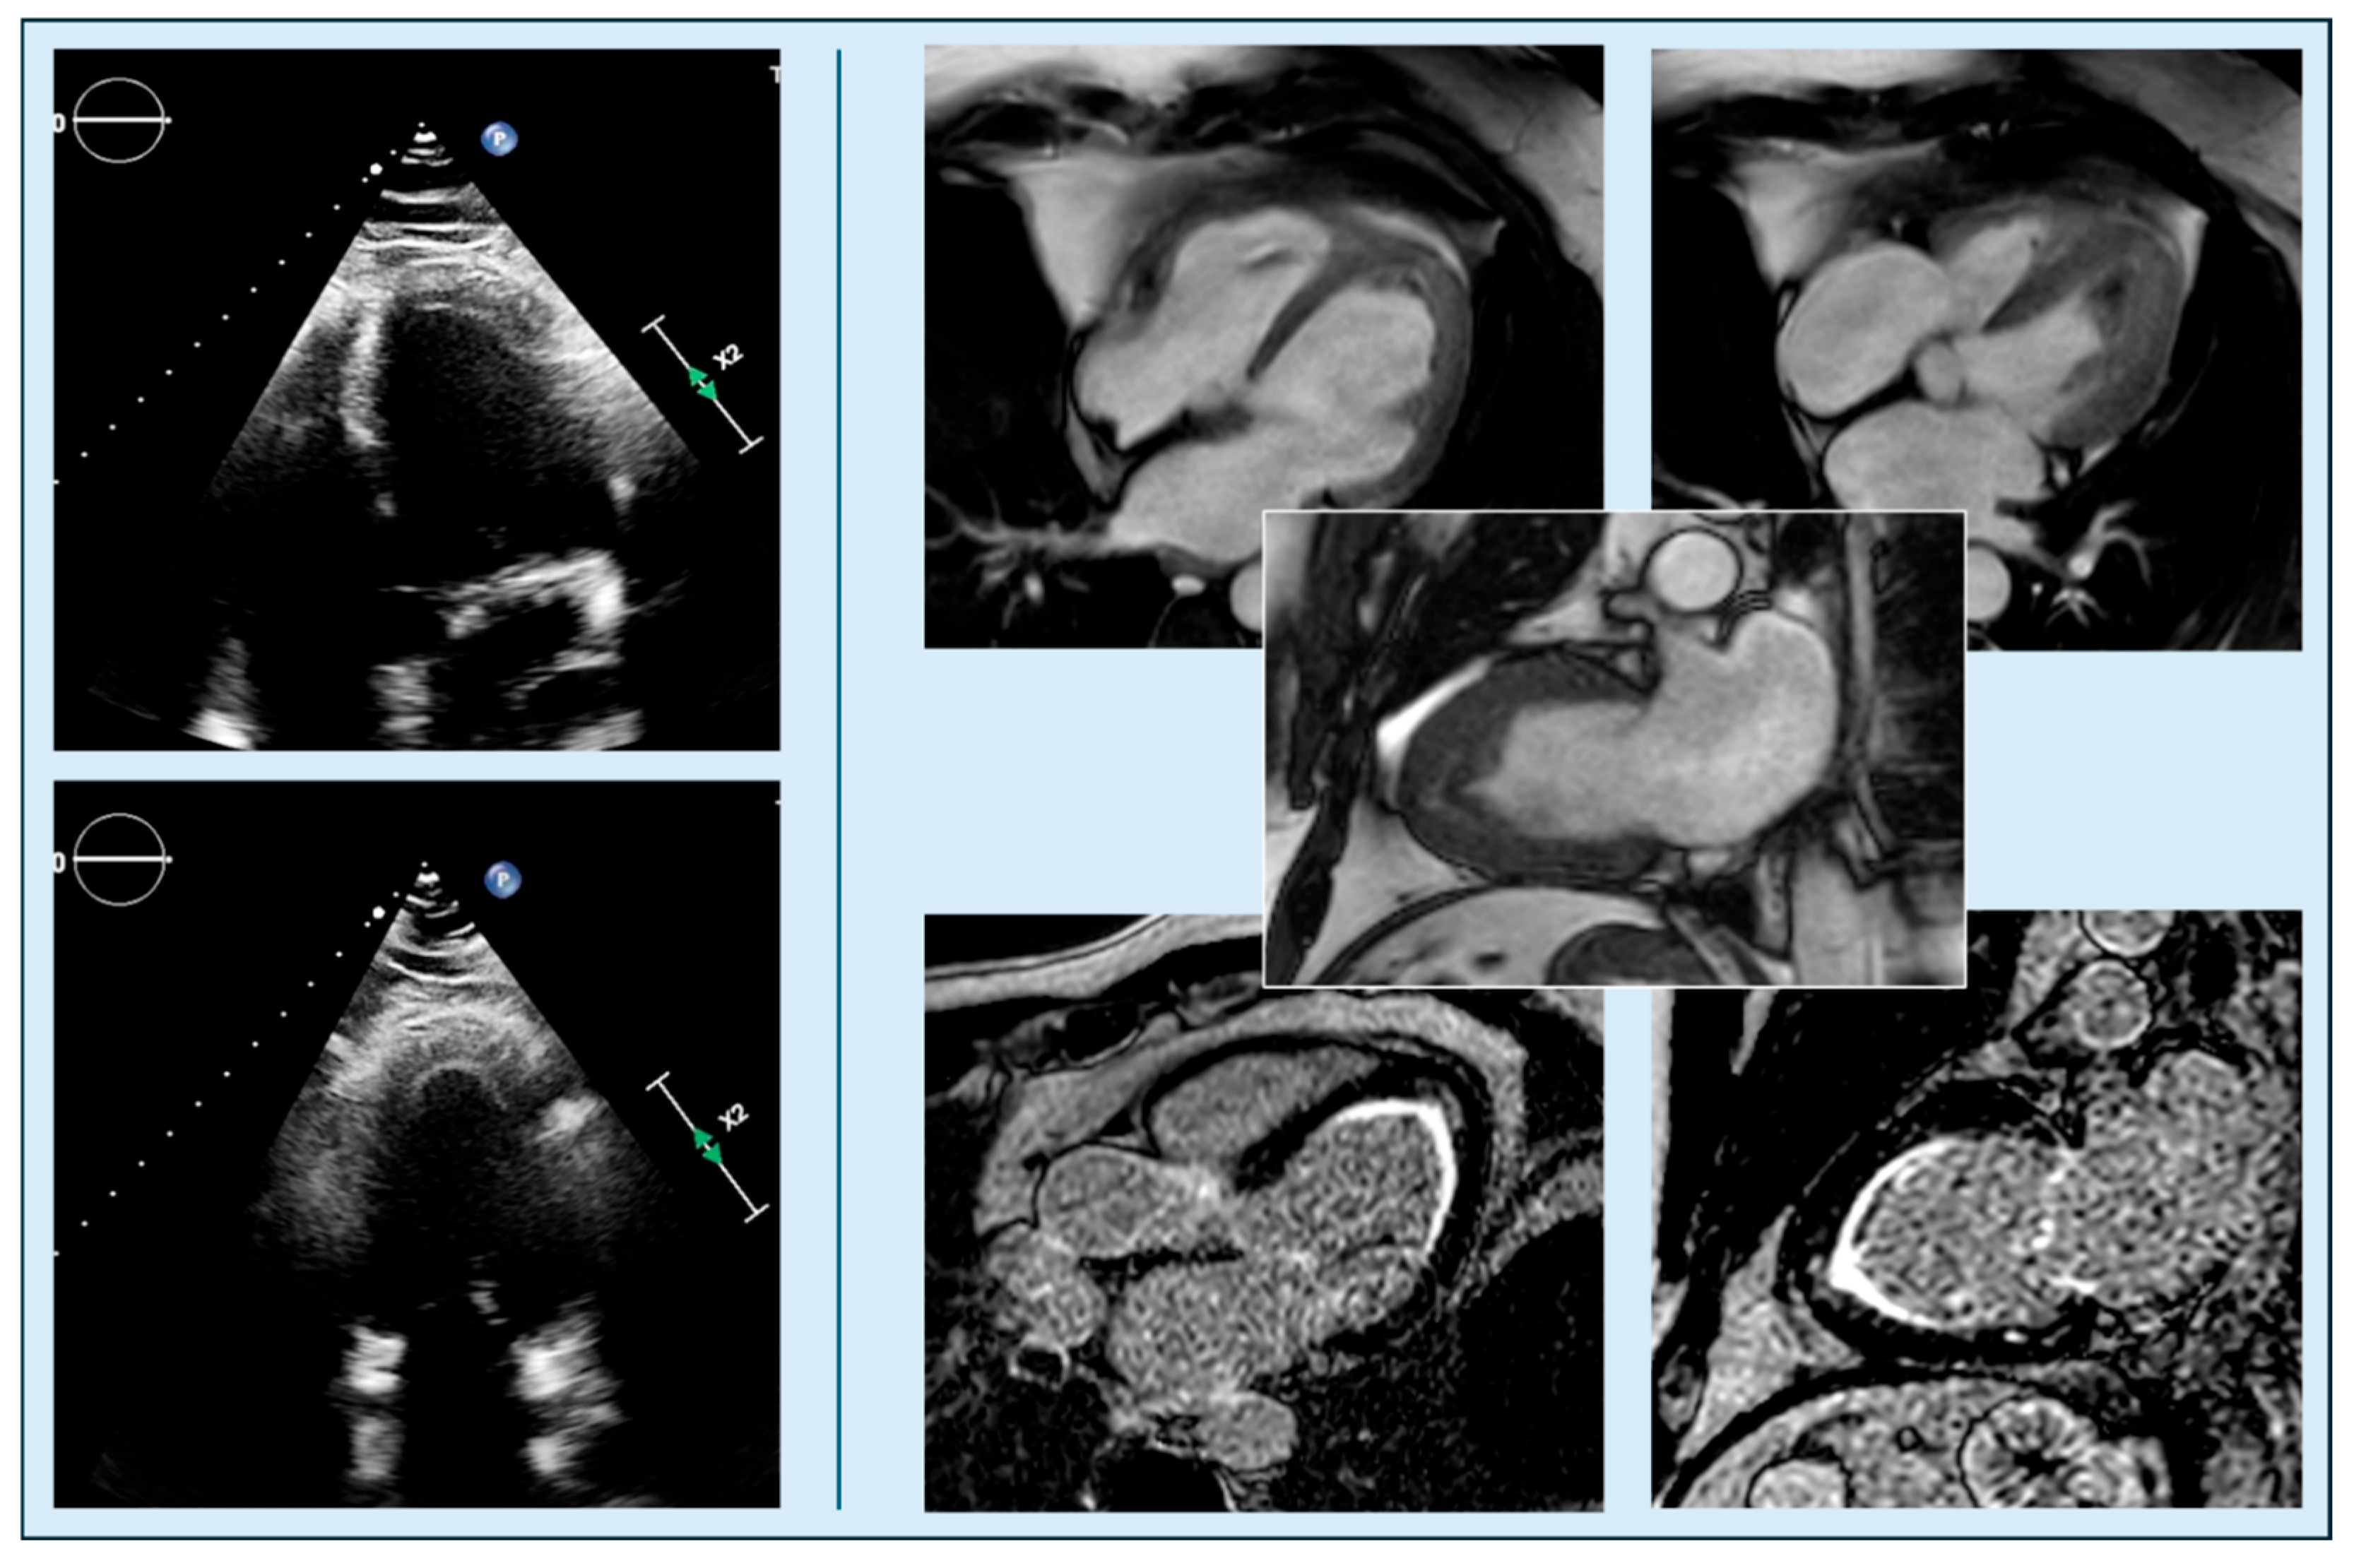

4.2. Apical Obliteration

- Kim, H.; Park, J.H.; Won, K.B.; Yoon, H.J.; Park, H.S.; Cho, Y.K. Significance of apical cavity obliteration in apical hypertrophic cardiomyopathy. Heart 2016, 102, 1215–1220. [Google Scholar] [CrossRef]

- Filomena, D.; Vandenberk, B.; Dresselaers, T.; Willems, R.; Van Cleemput, J.; Olivotto, I.; Robyns, T.; Bogaert, J. Apical papillary muscle displacement is a prevalent feature and a phenotypic precursor of apical hypertrophic cardiomyopathy. Eur. Heart J. Cardiovasc. Imaging 2023, 24, 1009–1016. [Google Scholar] [CrossRef]